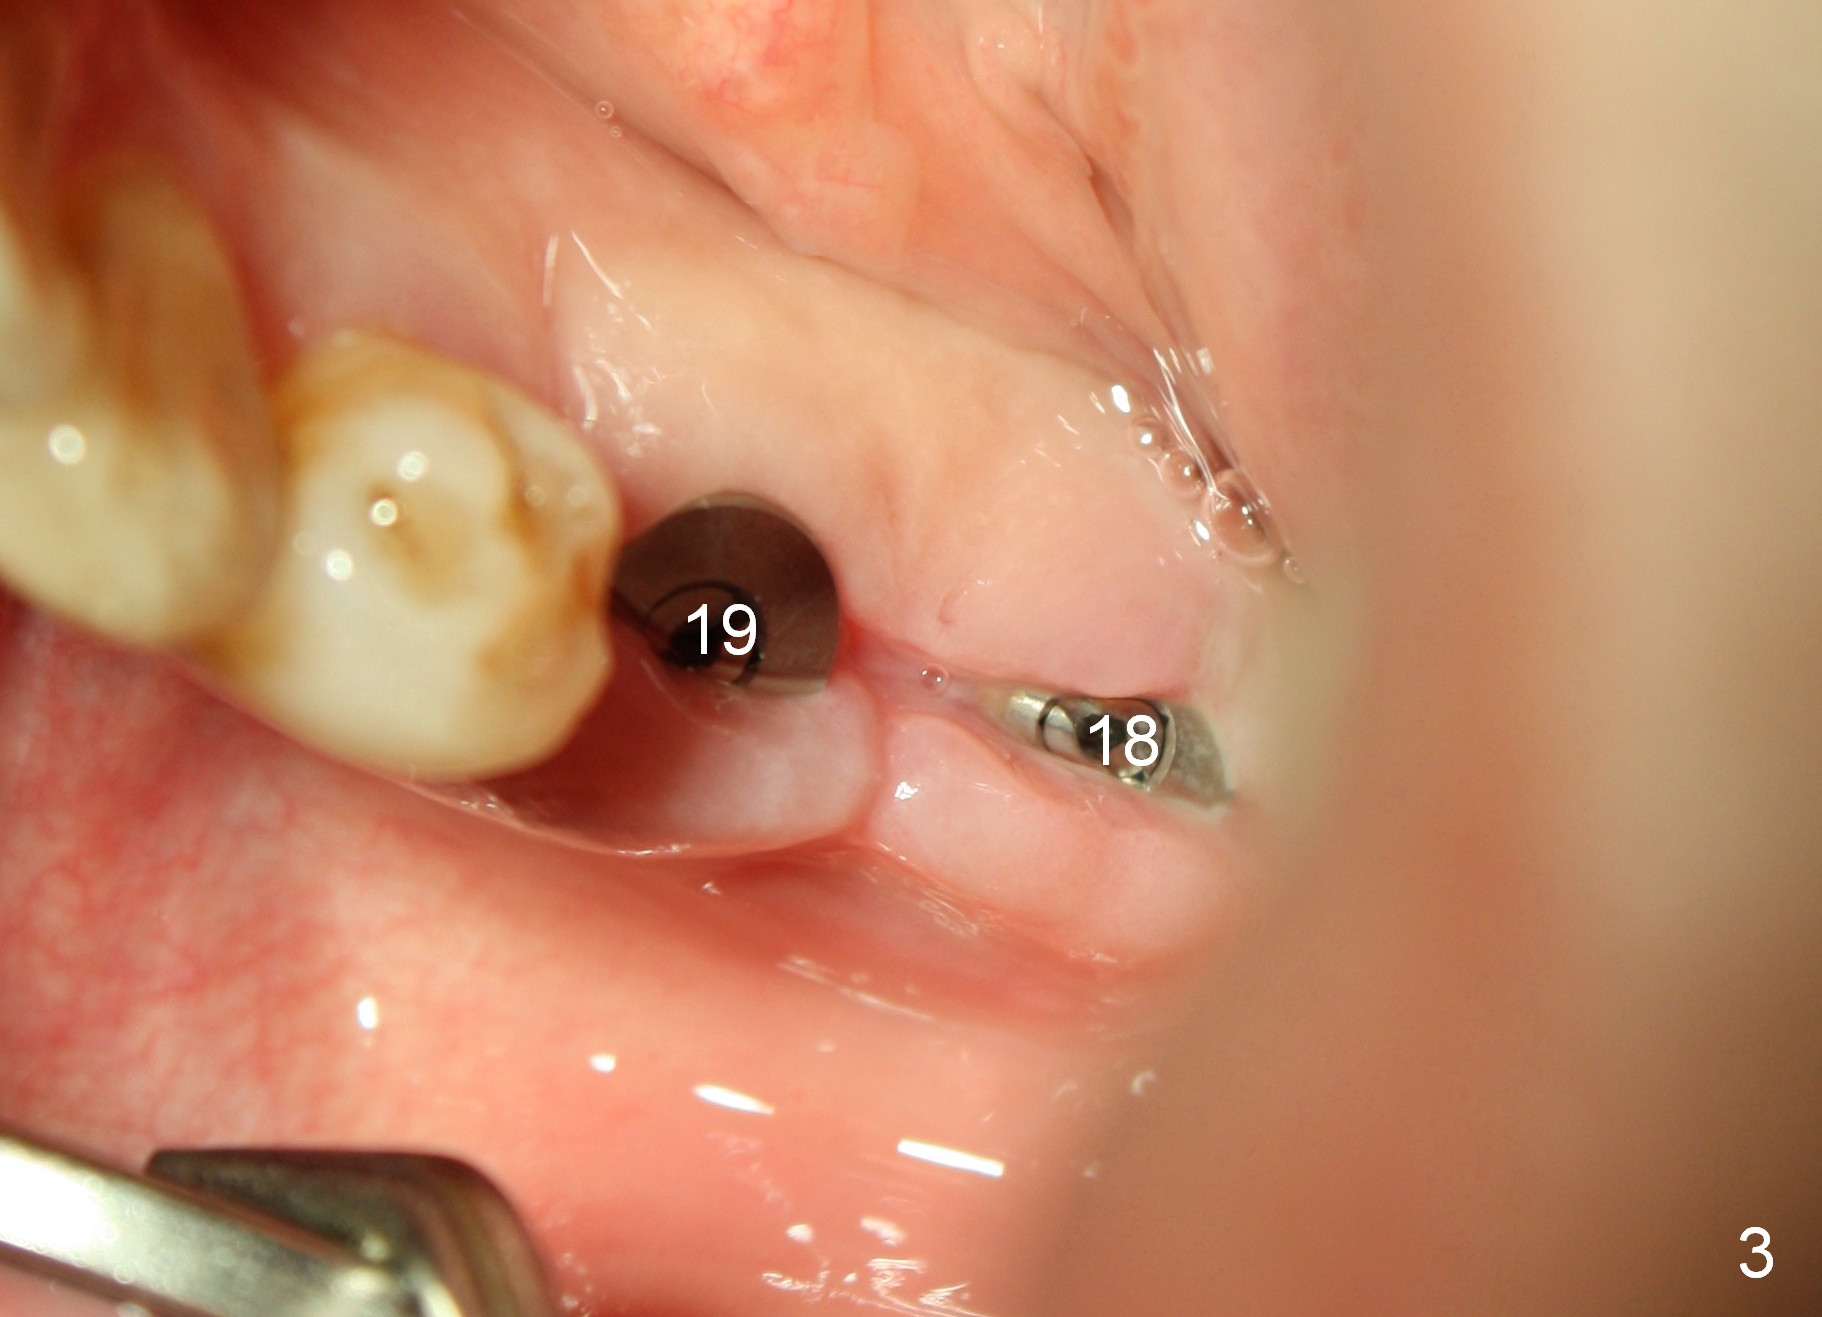

A 41-year-old man has chronic periodontits with bruxism. The teeth #14 and 15 are supraerupted (Fig.1 arrows) with furcal lesion (Fig.2 (CT) *). These 2 molars have guarded to poor prognosis. Due to insurance benefit limitation, we plan to save them temporarily with periodontal surgery so that bone loss would not get worse when the teeth are being intruded. After opposing implant placement (Fig.3), flaps are raised to remove calculus and granulation tissue (Fig.4, no bone graft). Twenty days later, three mini-implants are placed (Fig.5,6). The implant distopalatal to #15 is loose nearly 2 months postop (Fig.7 *) and retightened. The following month the same implant is placed higher for stability (Fig.8). The Intrusion takes <5.5 months (Fig.9,10).